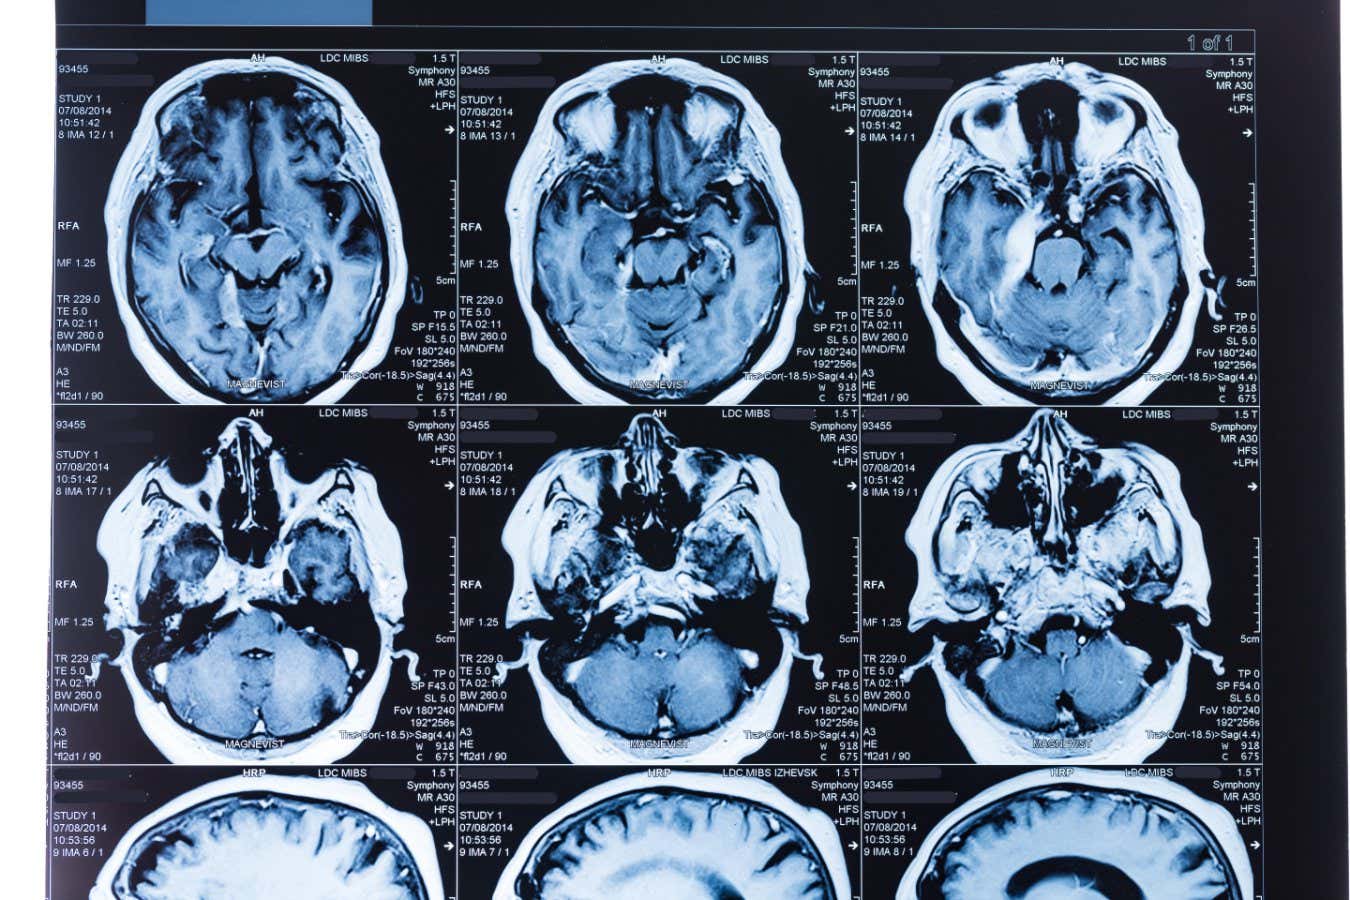

To get a broader idea of the effects of these proteins, Liu Weishi Researchers from Fudan University in China analyzed MRI brain scan data from around 11,000 adults (approximately 50 to 80 years old at the time of the images) who took part in the UK Biobank project.

Liu's team trained an artificial intelligence model using data from 70% of the participants to determine features of brain images, such as the size of different brain regions and how different parts are connected to each other. The age of the participants was predicted based on When the model was applied to the remaining 30% of participants, its predictions were accurate to within 2.7 years of their actual age.

The researchers then used the model to predict the age of another group of about 4,700 people, with an average age of 63, who also underwent brain imaging for UK Biobank. The researchers calculated the difference between these participants' actual ages and their AI-predicted ages, called the brain age gap. “The higher the age predicted by the AI compared to the actual age, the faster the brain ages,” Liu says.